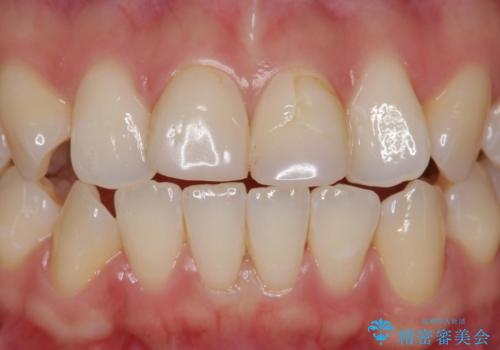

- 検査の結果虫歯が見つかった患者様です。

レントゲン画像と視診から詰め物で対応可能と判断したためインレーでの修復をしていきます。